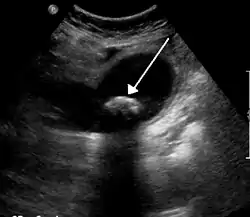

يتم الاعتماد على الأعراض ونتائج التحاليل في التشخيص، ولكن فحص الأشعة الصوتية يعتبر هو المعيار الذهبي في كشف الحصوات في منطقة ربع البطن العلوي الأيمن وذلك أنها خالية من الأشعة الضارة ومنخفضة التكلفة ومتاحة في معظم المنشئات الصحية، وتستطيع اكتشاف الحصوات بحساسية التقاط تفوق نسبة 95٪. [5] كما يمكن العثور على بعض الأدلة على التهاب المرارة أو حتى حصوات القناة الصفراوية المشتركة. [6] الأشعة المقطعية لا يوصى بها كوسيلة فحص للحصوات المرارية، حيث أنه ما نسبته 60٪ من الحصوات غير ظليل ولا يمكن كشفه بالأشعة المقطعية.